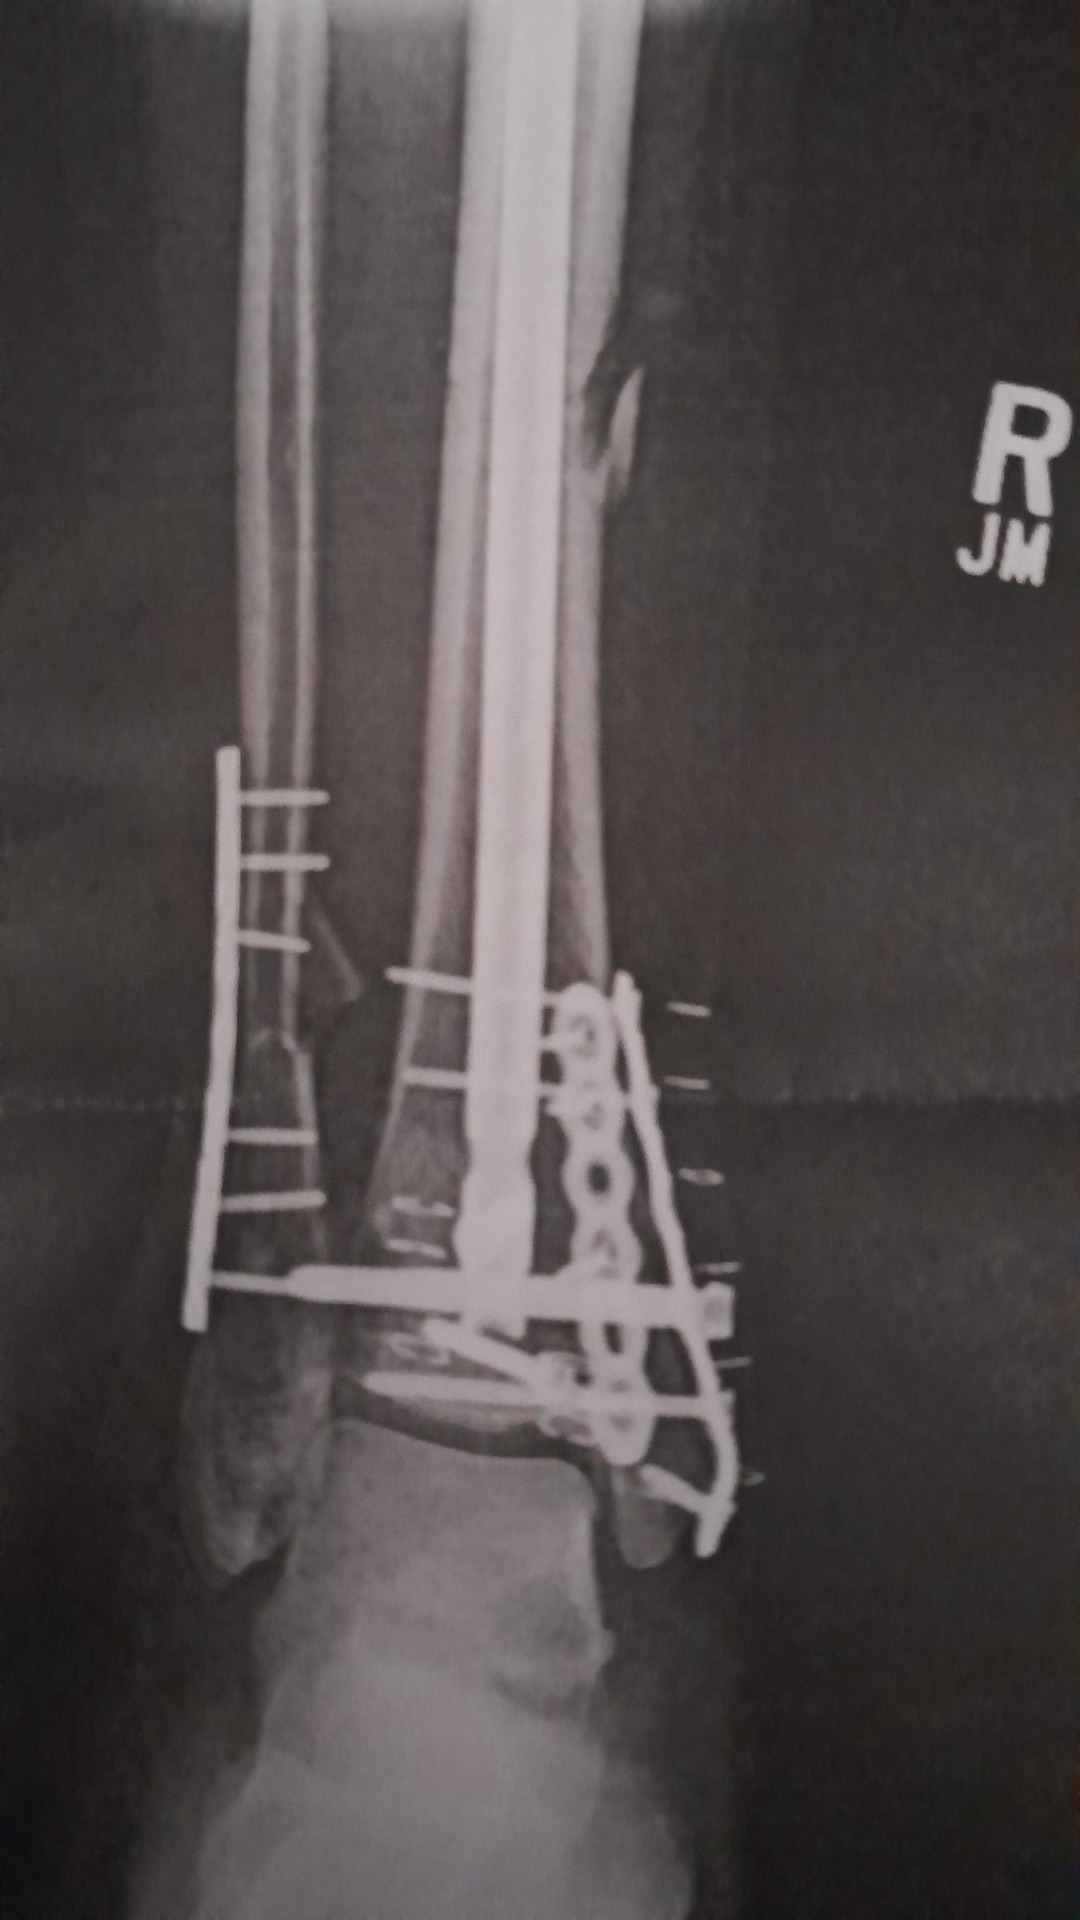

On August 29, 2025, Gregg was at his job at a big box home improvement store when he was seriously injured in a workplace accident. A lumber cart full of over 2000 lbs of lumber shifted, flipping the cart and its contents onto his right leg, crushing the lower leg and shattering the ankle. He was rushed to the Hurley Medical Center Trauma Unit where it was determined that he had an open fracture of the tibia and fibula, as well as a pilon fracture of the ankle. Gregg had external fixation surgery the next day to hold the bones in place to wait for the next operation which, due to other emergencies at the facility, he had to wait over 2 weeks for. At that point, a metal rod was put in through the knee with 3 plates and 15 screws in his leg and ankle. He was then released and in a wheelchair for 3 weeks, in extreme pain and unable to care for himself. While Gregg has a great support system in his fiancé Beth, family and friends, he has been unable to work, his savings are rapidly diminishing, and the amount he is receiving from workman's comp doesn't cover even his basic expenses, which is why we are reaching out for help. While Gregg is on the path to recovery and working his physical therapy, he is scared of what the long term implications will be on his life, the uncertainty of his future, his ability to walk, and to provide for himself and his family.